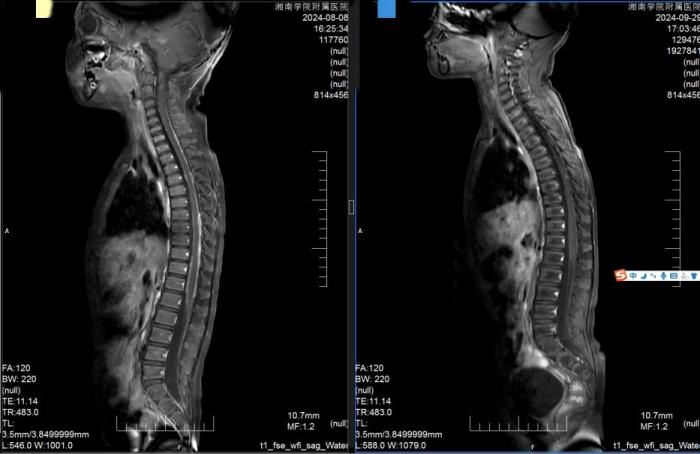

9月30日,经过6周的治疗,小俊的病情取得阶段性的胜利,复查小脑及脊髓多发病灶接近完全消失,顺利出院。

放疗前后小俊的磁共振图像对比